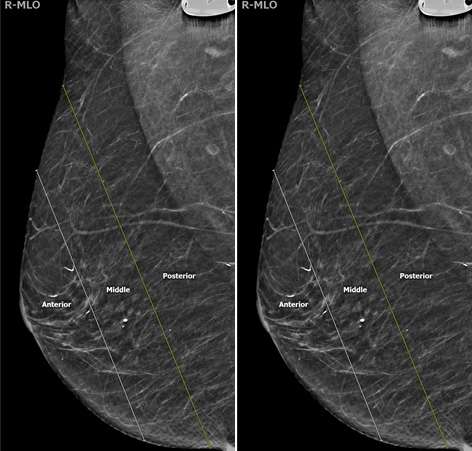

Two additional descriptors can be used to further help localize a lesion: depth within the breast and distance from the nipple. The breast is split into three layers of depth: anterior, middle, and posterior with each depth category representing approximately one-third of the breast tissue (Figure 7).

Screening Mammogram: Breast Lesion Localization Figure 7

Figure 7. The three different depths within the breast.